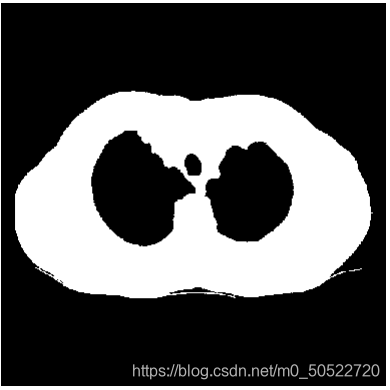

(5)肺质提取

由步骤4得到的图像肺质成像较好,但是肺质并没有与人体分离,此时就需要使用填充算法,首先将上图的图片进行二值图像孔洞填充,将整个人体组织填充,再使用填充后的图像减去上图中的图像就可以将肺质单独提取出来。

(6)消除气管

由上图可看出,虽然步骤5已经将肺质提取出来了,但是由于肺部中存在气管,所以在二值化以后会看到气管依然存在在二值图中,此时如果我们想得到没有气管的单独肺质时就需要对上图进行区域消除处理,定义一个适中的面积值,计算各连通区域的面积,由于肺质的连通面积较大,此时就使用定义的面积阈值,将小于此面积阈值的部分消除。即可得到单独的肺质如下图所示。